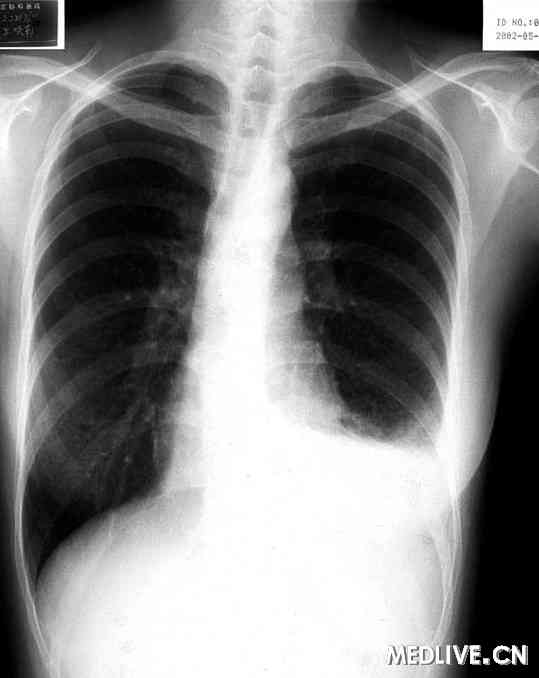

图2 X线胸片左侧胸腔积液

总结本例有如下特点:⑴女性,28岁。⑵因低热、咳嗽、左胸痛入院。⑶左侧气胸一次。⑷左侧乳糜胸(见图2)。⑸胸部HRCT示双肺弥漫性薄壁囊性改变。这些临床特点强烈提示LAM的可能。患者在入院前主要的临床发现为乳糜胸,临床医师忽视了气胸史,普通CT上也未发现双肺的囊性改变。因此当时诊治的重点为乳糜胸,并给予了抗结核治疗。